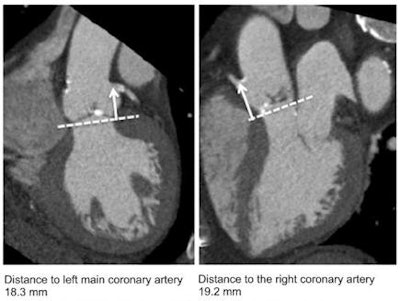

Bax's colleague from the Leiden center, Dr. Victoria Delgado, PhD, described in detail the critical role cardiac CT plays in the planning and follow-up of TAVI patients. In a first step, cardiac CT can confirm the severity of aortic stenosis and also is essential for determining the feasibility of the procedure with measurement of the aortic valve dimensions and aortic root anatomy. The maximum and minimum annular dimensions are key to the selection of the appropriate valve replacement, and the distance to the coronary ostia is critical in procedural success and the eventual need for a pacemaker after placement of the prosthesis.

Cardiac CT measurement of aortic root anatomy